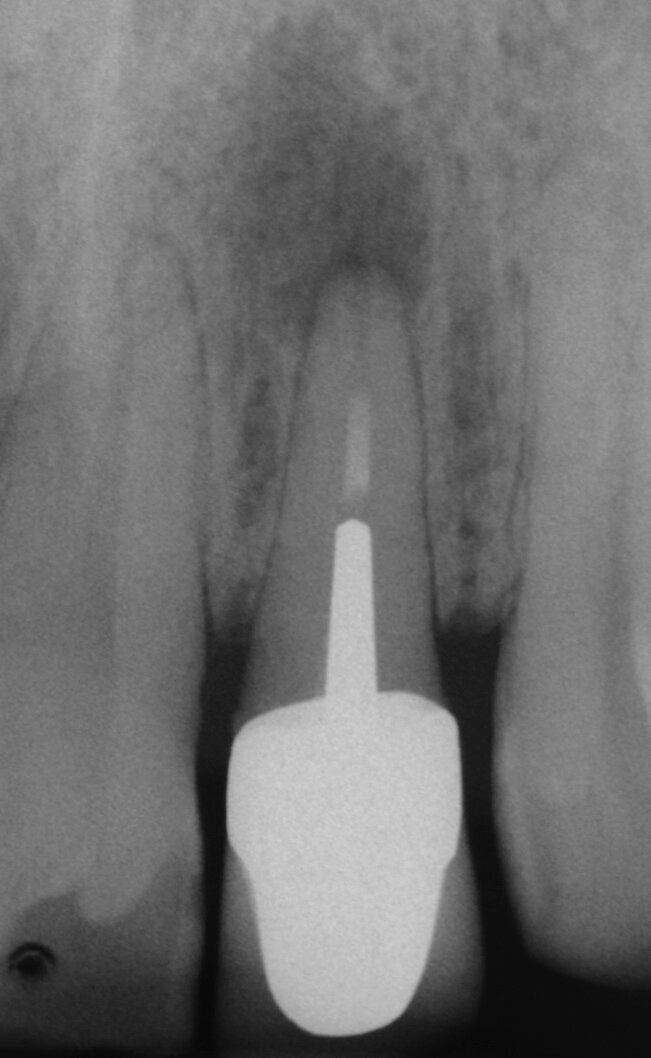

In combinazione con MAP System, Produits Dentaires offre un MTA bianco appositamente sviluppato per il posizionamento con i puntali MAP. Le dimensioni pratiche ottimizzate consentono un’applicazione economica per ogni trattamento. Ci sono molte indicazioni per il PD MTA White, e con il sistema MAP il corretto posizionamento è facile in ogni situazione (Figg. 2a-2g).

Per evitare l’estrusione di materiale da otturazione del canale radicolare in denti immaturi con apici aperti, si utilizza MTA come sigillo apicale. I risultati di molti studi hanno dimostrato che l’MTA induce più spesso la formazione di tessuto duro apicale e che il suo uso è associato ad una minore infiammazione rispetto ad altri materiali di prova (Simon et al. 2007) (Figg. 2a-2g).